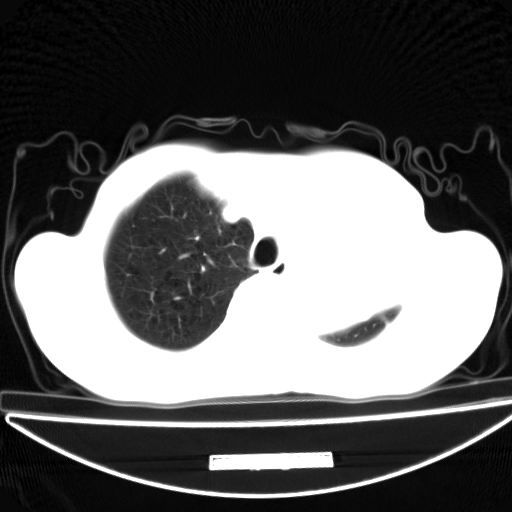

以下是引用杀毒软件在2009-4-28 17:58:00的发言:[br]考虑----左肺慢性肺脓肿形成继发上叶含气不良---抗炎后复查---待排肿瘤所致[br][br][本贴已被 杀毒软件 于 2009-4-28 18:01:26 修改过]